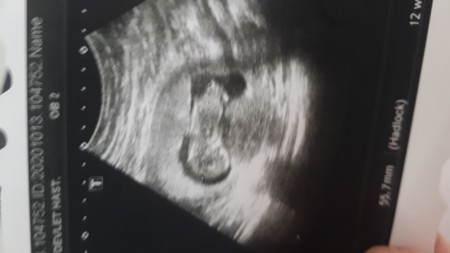

Acaba cinsiyeti ne ilk gebelhm ck merk edyrm saglikla glsn inslhl

Kız bu '.)

Daha çok erken ama erkek gibi canim :)

Aynı benim bebeğim gibi durmuş aynen böyle benimde ultrason kağıdım var ve erkek ben erkek diyorum artık öğrenince yazarsın buraya

%50 Kız

%50 Erkek